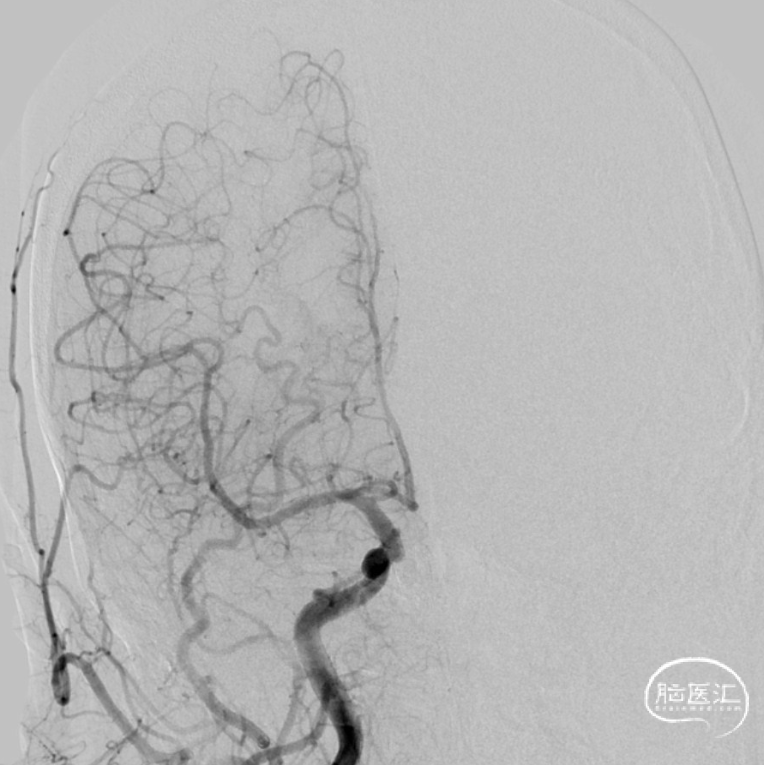

治疗经过